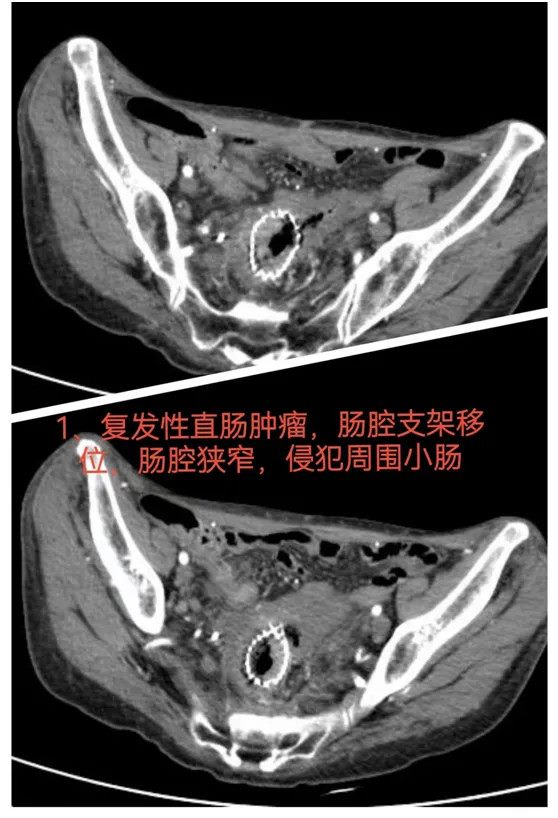

01复发性直肠癌侵犯空肠,精准手术力挽狂澜

患者,男,65岁,1年多前因直肠癌在外院接受了手术治疗。术后3个月,患者出现了不全性肠梗阻,经介入治疗后成功置入肠道支架,腹胀症状有所缓解。但患者仍间歇性出现腹痛不适,症状未能完全消失。入院后,肠镜检查发现直乙吻合口处出现肿物,支架移位,提示肿瘤复发。术中进一步探查显示,肿瘤不仅在直肠肿瘤复发,还已侵犯到空肠。面对这一挑战,手术团队决定采用腹腔镜技术进行精确手术,成功切除了复发肿瘤,同时对侵犯小肠进行切除,并在术后进行了盆底补片修补重建术。手术顺利完成,患者术后恢复良好,腹部症状明显减轻。

难点总结:该病例的关键难点在于肿瘤的复发且侵犯空肠,通过腹腔镜操作,团队成功完成了肿瘤的根治性切除,并通过盆底重建术预防了术后肠梗阻的发生,效果显著。

推荐理由:该病例展示了复杂肿瘤复发及多器官受累情况下的精准手术方案。通过腹腔镜技术的巧妙应用,手术团队不仅成功完成了肿瘤的根治性切除,还有效预防了术后并发症的发生。